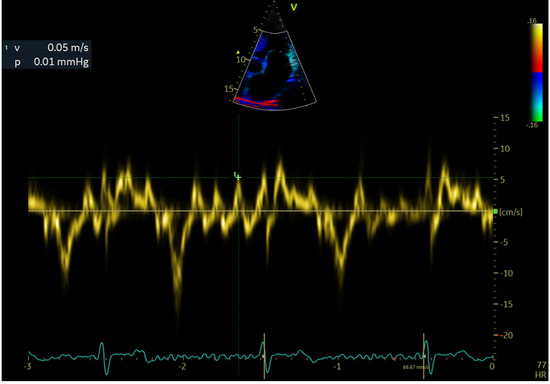

2.4. Echocardiographic Evaluation

| LAWMV (cm/s) | 3.22 (1.07) | 3.69 (0.84) | 2.86 (1.09) | <0.001 |